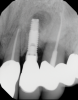

In this case, a dental implant that had been placed 10 years prior was functional, stable, and esthetically acceptable to the patient. However, a significant fistula was present on the facial-apical aspect of the ridge in the maxillary lateral incisor area. This area was painfully sensitive to touch and demonstrated purulence when squeezed. To evaluate the lesion, first, a conventional digital radiograph was acquired, which revealed an apical radiolucency at the apex of the implant (Figure 1). Further analysis using cone-beam computed tomography (CBCT) demonstrated a fistula from that site to the oral environment (Figure 2). Treatment options were discussed, including removal of the implant, followed by grafting, a healing period, and replacement of the implant and implant-retained crown. If this option was selected, a transitional appliance would need to be created. Another option was to attempt to salvage the implant and implant crown by treating the infection and grafting the site to create a new boney wall and eliminate the fistula. Ultimately, the patient accepted this option to attempt to salvage the fixture and crown.

(2.) Preoperative CBCT analysis demonstrating a fistula from the site of the radiolucency to the oral environment.

Figure 2